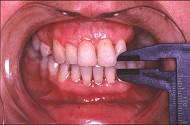

患儿,5岁,外伤后逐渐出现张口困难,咬合关系错乱,髁突动度减弱,外观及X 线检查结果如图。最可能的诊断是 ( )

患儿,5岁,外伤后逐渐出现张口困难,咬合关系错乱,髁突动度减弱,外观及X 线检查结果如图。最可能的诊断是 ( )![]()